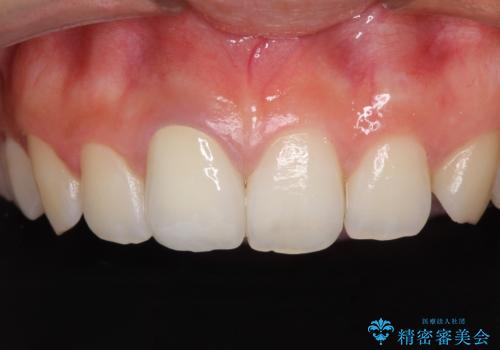

あっという間に気になっていた変色が解決し、早く治療を始めれば良かったとおっしゃっていました。

オーダーメイドタイプのクラウンを選択いただいたので、まるで天然の歯と見間違うほど自然に仕上がり、患者様には大変満足していただきました。